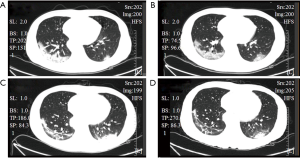

A 41-year-old man was admitted to a fever clinic on January 27, 2020, with symptoms of fever, chills, cough, fatigue, and shortness of breath. On January 22, 2020, he traveled from Henan to Guangzhou via Wuhan by a high-speed train and then to Xinyi by a bus. January 23, 2020, was the first day of his onset, with initial symptoms of mild chills and dry cough, but he did not visit a doctor but stayed at home until January 27, 2020 (Figure 1). The CT image of this man four times is shown in Figure 2. He presented to an urgent care clinic in Xinyi County, Maoming, with a 5-day history of cough and subjective fever. Chest computer tomography (CT) showed multiple patchy shadows in both lungs, consistent with COVID-19 changes in the right upper and lower lungs and the left lower lung (Figure 2A), and a throat swab sample was obtained. On January 29, 2020 (day 7 of illness), the Maoming Centers for Disease Control (CDC) confirmed that the patient had COVID-19 by reverse real-time PCR assay. Written informed consent was obtained from the patient for publication of this Case report and any accompanying images. All procedures performed in studies involving human participants were in accordance with the ethical standards of the institutional and/or national research committee(s) and with the Helsinki Declaration (as revised in 2013).

Immediate admission to the isolation ward and supplemental oxygen via a mask [high-flow cannula oxygen therapy (HFNC) (50% concentration, 40 L/min)] were conducted. Aerosol inhalation of interferon α-2b (5 million units twice a day), lopinavir plus ritonavir (500 mg twice a day), and oseltamivir (75 mg twice a day orally) was given for antiviral therapy; moxifloxacin (0.4 g once a day, intravenous injection) for secondary infection prevention. On the second day after admission, the patient was attended by a skilled TCM practitioner for the first time, and he assessed the tongue diagnosis (Figure 3, Table 1). He received TCM decoction (Gegeng with Xiaocaihu, daily). On February 01, 2020 (day 10 of illness), the disease had progressed. The patient developed severe dyspnea and was transferred to the ICU. Methylprednisolone (40 mg twice a day, intravenous injection) was administered to attenuate lung inflammation considering the severe shortness of breath and hypoxemia. Laboratory test results are listed in Figure 4. After receiving medication, his body temperature reduced from 39.0 to 36.4 °C. However, his cough, dyspnea, and fatigue did not improve. A chest CT scan showed progressive infiltrate and diffuse gridding shadows in both lungs (Figure 2B). He had received non-invasive ventilator support in the ICU; therefore, he received HFNC (60% concentration, 50 L/min). At that time, the patient was attended by a skilled TCM practitioner for the second time (Figure 3, Table 1), and he received another decoction (Chaihu + Sanren, daily). On the 12th day of onset, the patient showed symptomatic improvement with oxygen saturation above 95%. The patient was attended by a skilled TCM practitioner for the third time (Figure 3, Table 1), and he received the third decoction (Chaihu + Sanren, daily). On the 14th day of onset, his hypoxemia and shortness of breath improved. The patient was attended by a skilled TCM practitioner for the fourth time (Figure 3, Table 1), and he received another decoction (Xiaochaihu + Maxingshigan). A chest CT scan showed that the left lower lung lesions had increased, enlarged, and combined, and the right upper and lower lung lesions were slightly absorbed (Figure 2C). The oxygenation index rose from 195 to 325 on February 1, 2020 (Figure 5). On day 16 of illness, the symptom of dyspnea continued to improve (Figure 5). The patient was transferred out of the ICU. The patient stopped using lopinavir and ritonavir, and he received antiviral therapy with abidol and strengthened albumin infusion to correct the low protein level in blood. The patient was attended by a skilled TCM practitioner for the fifth time (Figure 3, Table 1), and he received another decoction (XiaoChaiHu + Maxingshigan + Xiaoxianxiong). On days 18, 20, and 22 of illness, the patient was attended by a skilled TCM practitioner three times (Figure 3, Table 1), and he received decoction. His symptom of dyspnea continued to improve. A chest CT scan showed that the bilateral lung lesions were absorbed more than before (Figure 2D) on February 10, 2020. Finally, the patient was cured and discharged from the hospital on February 13, 2020.